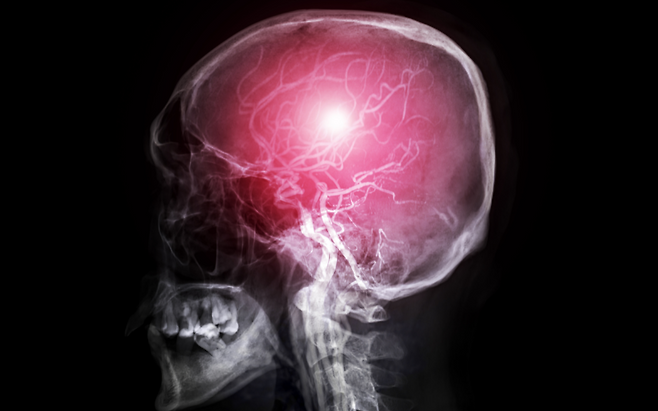

비 내리는 소리에 창문을 닫고 나면 실내는 오히려 ‘습기 폭탄’으로 변합니다. 습도계 바늘이 70%를 넘기는 순간 눈 뒤가 당기고 맥박이 귀에서 울리며 편두통이 폭발적으로 시작됩니다.

높은 습도는 뇌혈관을 수축·팽창시키는 자율신경을 혼란에 빠뜨려 치명적 통증을 유발하고, 방치하면 일상이 순식간에 무너집니다. “비 오는 날 머리가 깨질 듯 아프다”는 말은 단순 징얼거림이 아니라 과학적 경고음입니다.

실내 습도가 70%를 넘으면 체열 발산이 어려워져 체온이 미세하게 상승하고, 뇌혈관은 온도 변화를 보상하려고 급격히 수축·확장합니다.

이 과정에서 삼차신경이 자극받아 편두통이 발화하며, 수축 상태가 길어지면 산소 공급이 20% 이상 줄어 두통 강도가 배로 치솟습니다.

장마철 기압 하강은 이미 혈관을 확장시키고 있는데, 고습 환경이 겹치면 자율신경이 균형을 잃어 진폭 큰 수축·이완 사이클이 반복됩니다. 이 ‘롤러코스터 효과’는 뇌신경 염증 매개물질을 폭증시켜 구토·현기증까지 동반하는 치명적 복합 두통으로 이어집니다.